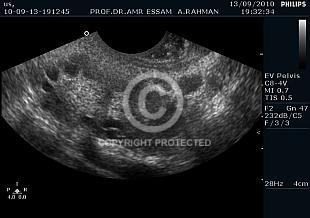

Uterine anomalies